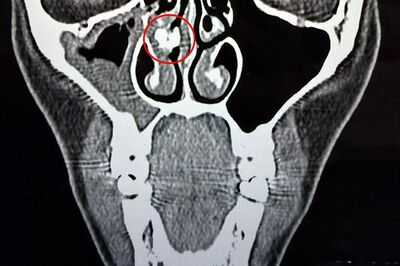

“He ordered another CT scan, and this time I got it done. The report mentioned a ‘partially calcified focal image of approximately 8x6mm’ suggestive of a rhinolith, which is basically an encapsulated foreign body.

“When I brought the scan in, the doctor examined me with an endoscope and located the obstruction.” She added: “After almost an hour of trying to remove it, he finally managed to extract it with forceps.”